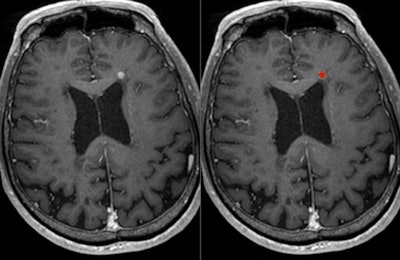

Postgadolinium T1-weighted image shows lesion (left: original image; right: lesion marked in red).Most of the controversies regarding the use of gadolinium focus on the primary diagnosis -- rather than follow-up and post-treatment -- of vestibular schwannoma, which is a benign intracranial tumor of the myelin-forming cells of the vestibulocochlear nerve in the internal auditory canal next to the brain. Patients may present with sensorineural hearing loss, tinnitus, and balance problems, but only a small percentage of people with these symptoms will have vestibular schwannoma, explained Dr. Berit Verbist, a neuro and head and neck radiologist at Leiden University Medical Centre in the Netherlands.